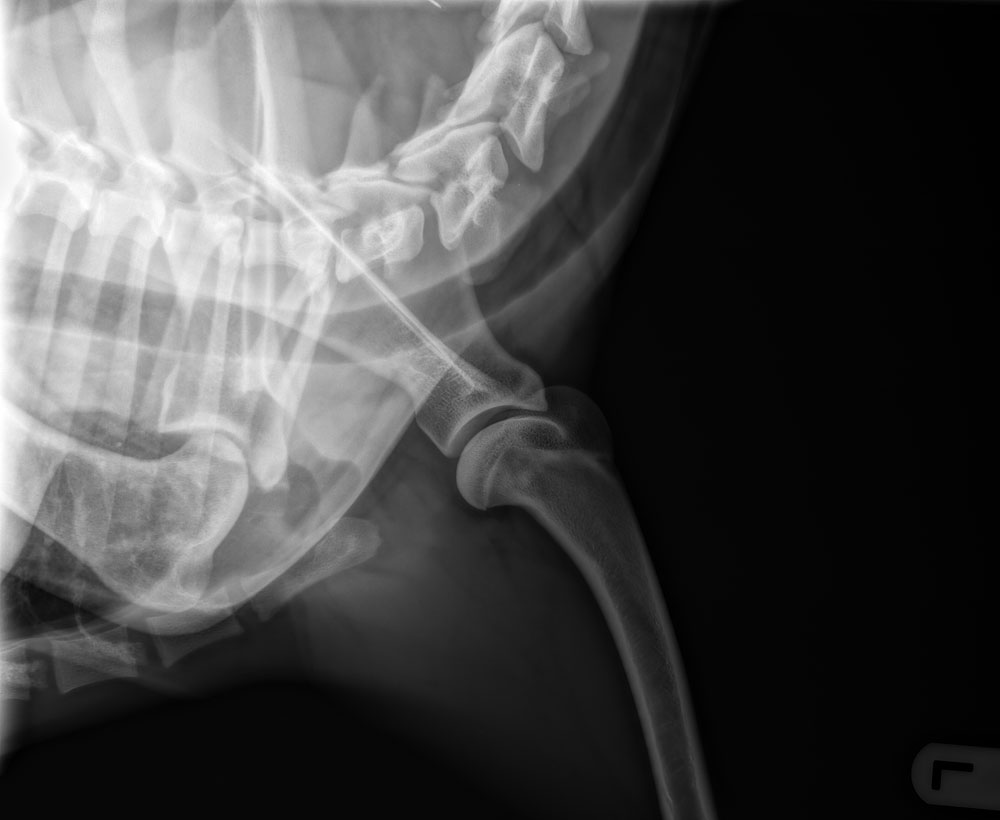

| HD : | HD-A (Norb.waarde 32,5, botafw. 0, goede aansl.) Pennhip: DI=0.19 (details + uitleg) | |